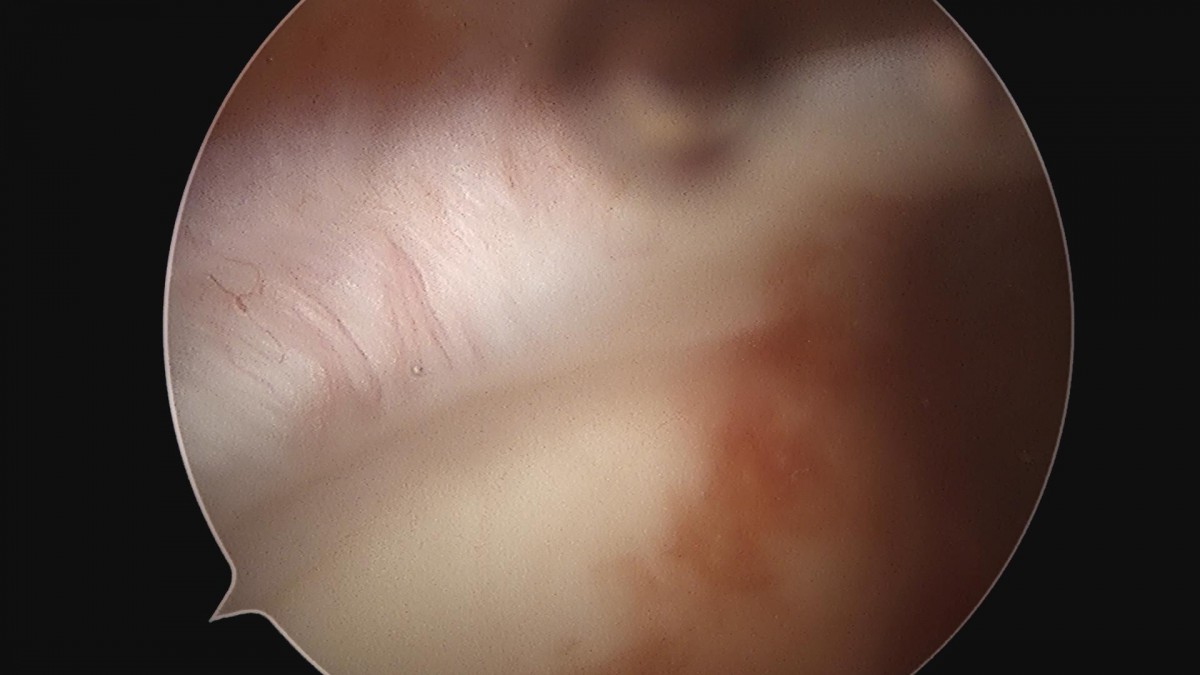

하윤원원장님 어깨 활액막제거술 및 견봉성형술 정지O 환자

작성자 최고관리자 댓글 0건 조회 2,170회 작성일 23-03-16 10:44